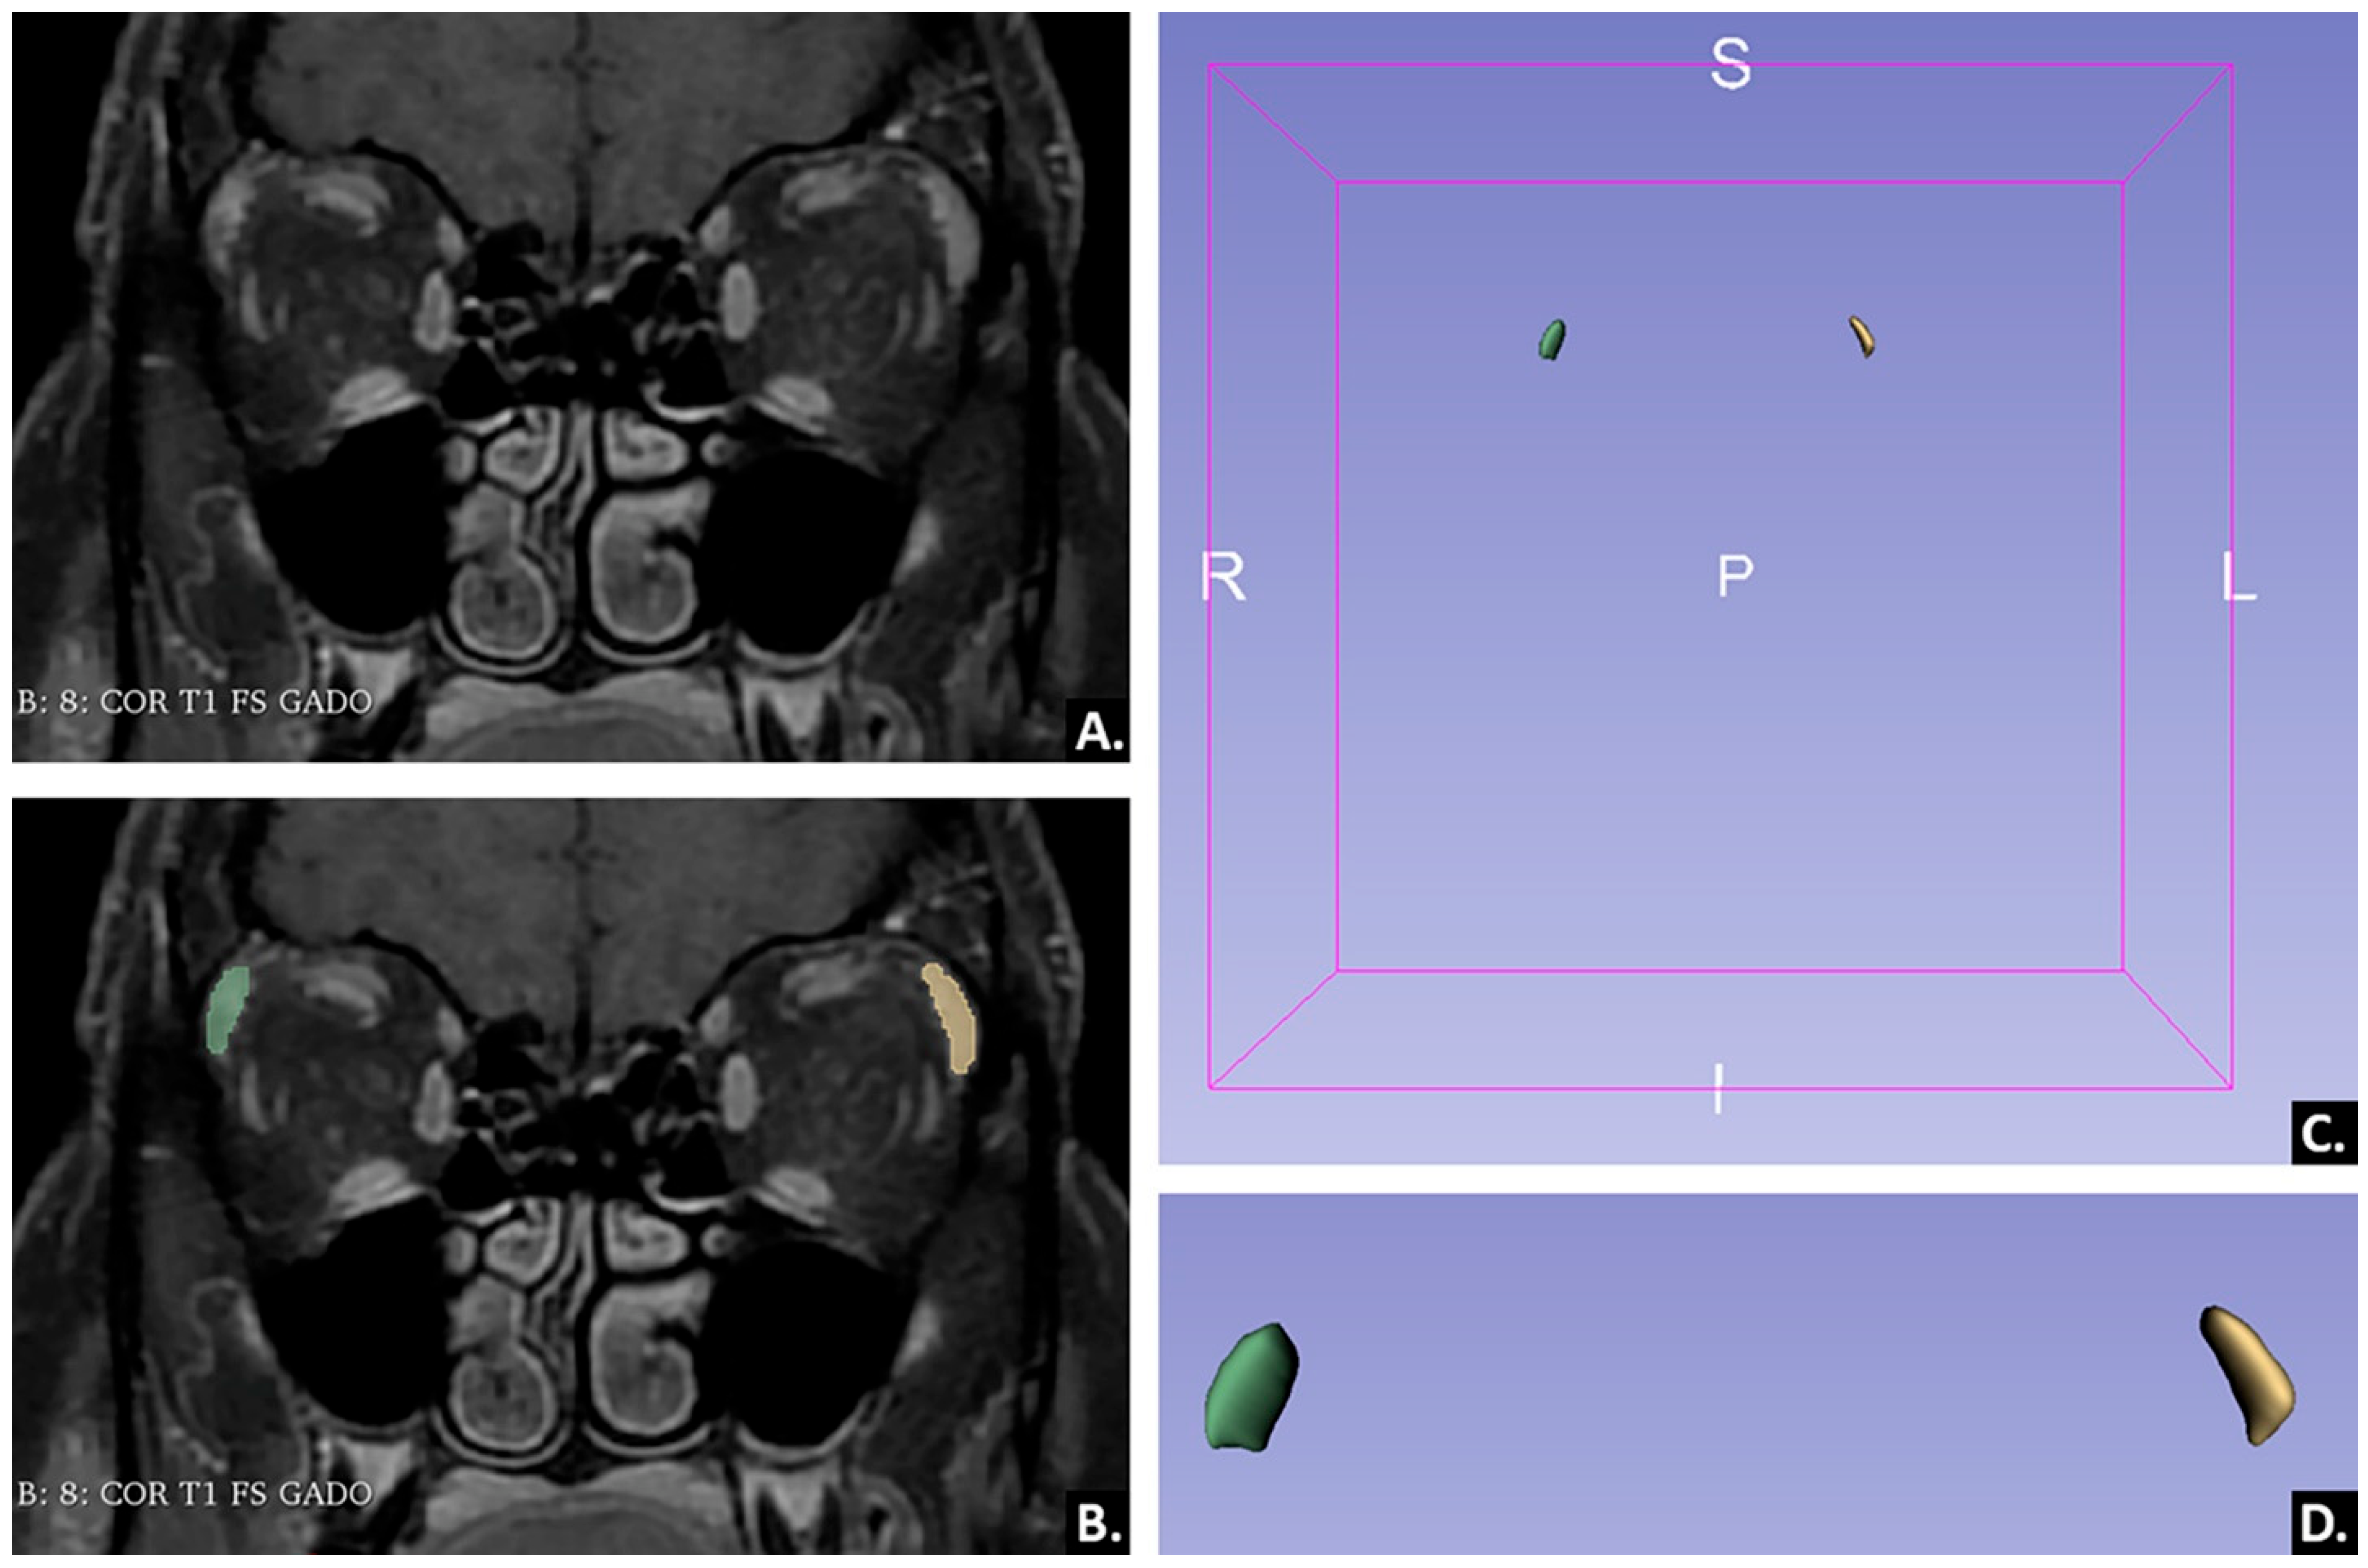

4.3.1. Image Pre-Processing and Segmentation